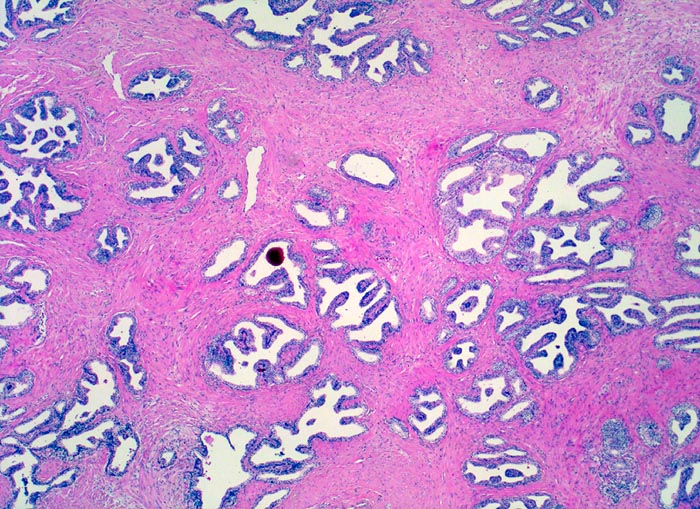

Normale Prostatadrüsen

Das normale Prostataparenchym besteht aus regelmässig angeordneten Paketen grösserer Drüsen eingebettet in glatte Muskulatur. Die Drüsen enthalten oft eingedicktes und verkalktes Sekret.

25